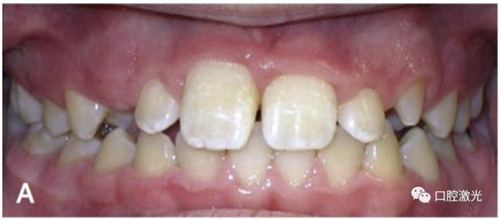

改善口腔衛(wèi)生狀況

有時,會遇到一些口腔衛(wèi)生問題比較嚴重的患者,從而導致牙齦發(fā)炎而腫大。通過改善口腔衛(wèi)生環(huán)境,炎癥可以得到緩解,但增生的牙齦不一定都可以完全恢復。下圖的患者就存在口腔牙齦肥厚問題,同時左上部犬牙存在部分萌出的問題,右上部犬牙存在未萌出問題,這些問題都妨礙了托槽的粘接。因此,實施了全口腔的牙齦整形手術(shù)。去除了多余的牙齦組織,增加了犬牙的暴露面積,從而使托槽的粘接更為便利,同時也提升了患者保持口腔衛(wèi)生的狀況。

治療前